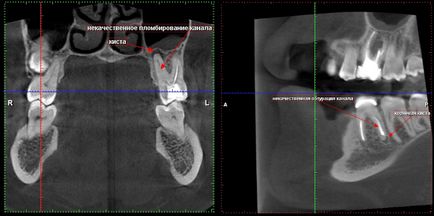

Minősége gyökértömés (töltési) csatornák és a jelenléte cisztás folyamatok körül tetejét a fogak